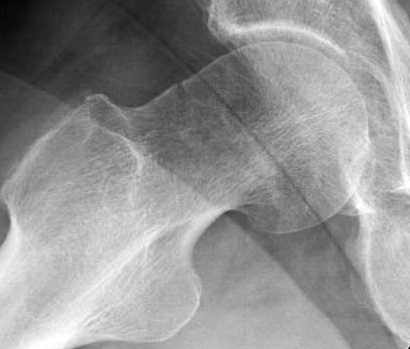

Почему неполный перелом? Я бы назвал его вколоченным!

Перелом конечно не вколоченный т.к. видно линию перелома и нет суперпозиции костной ткани.

На второй день после выписки упал дома. Снимки приложены. Коллеги рекомендуют удаление шурупа и вытяжение. Что делать?